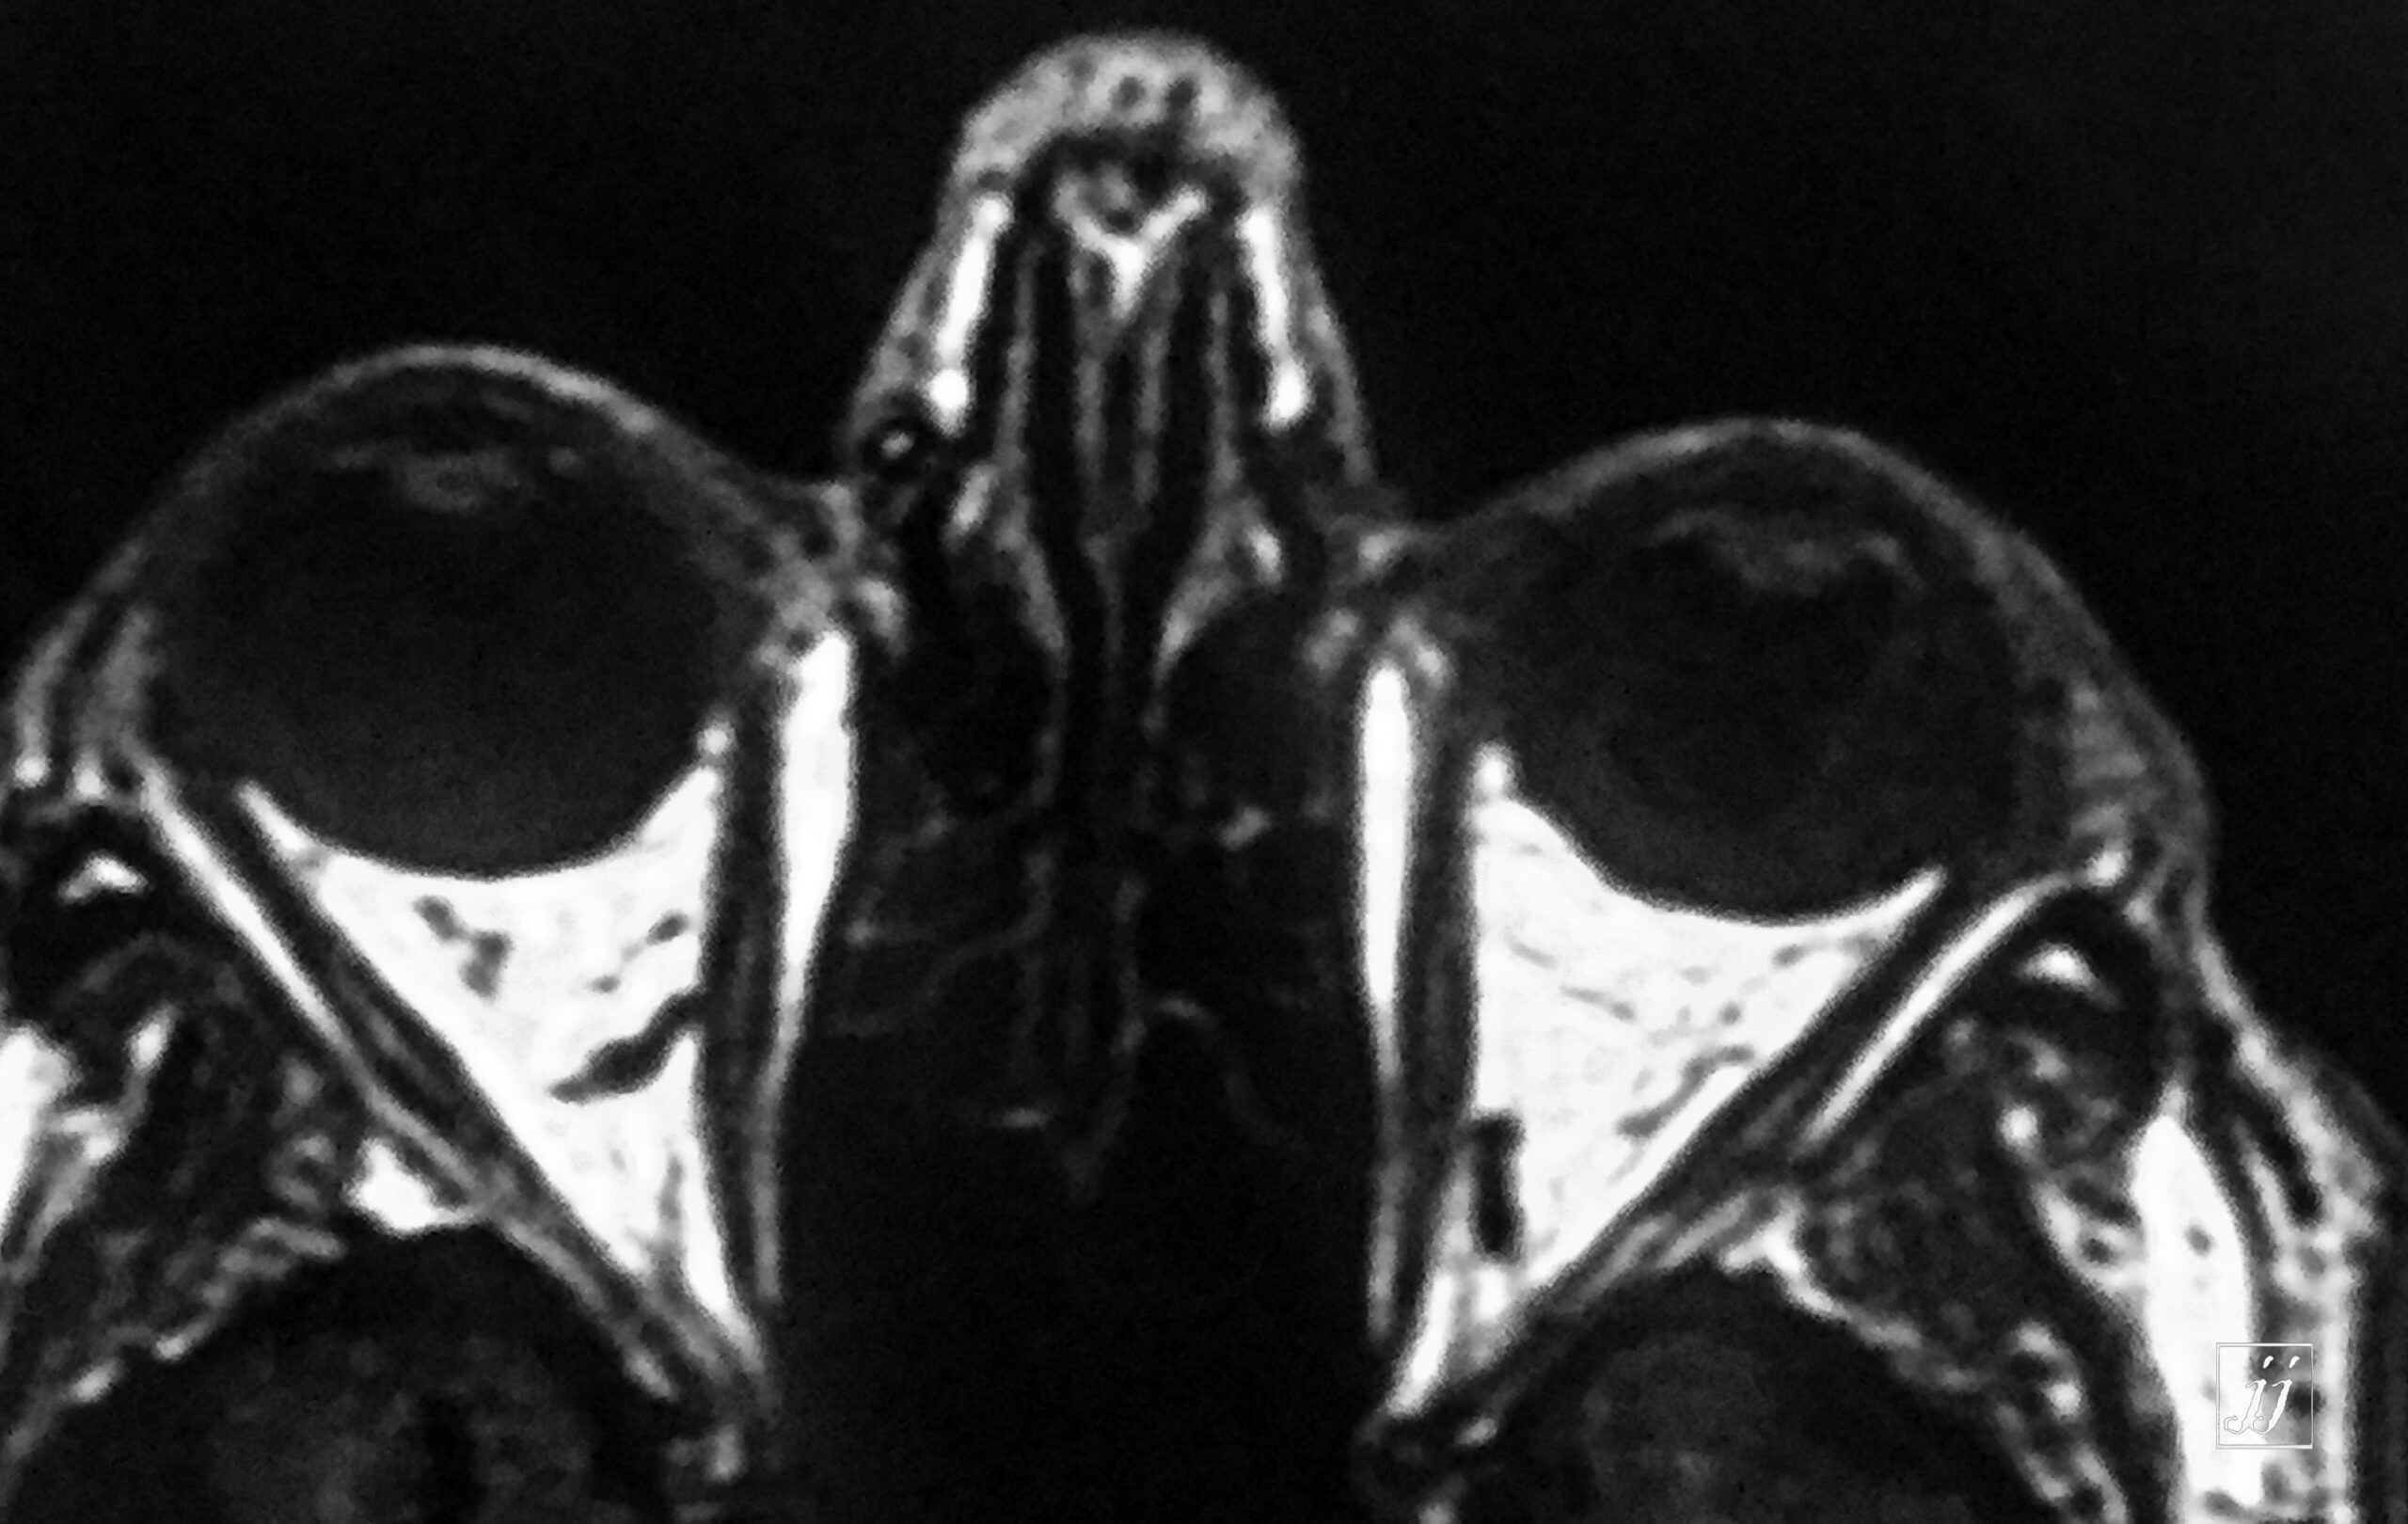

Orbit- vitreous detachment (1)